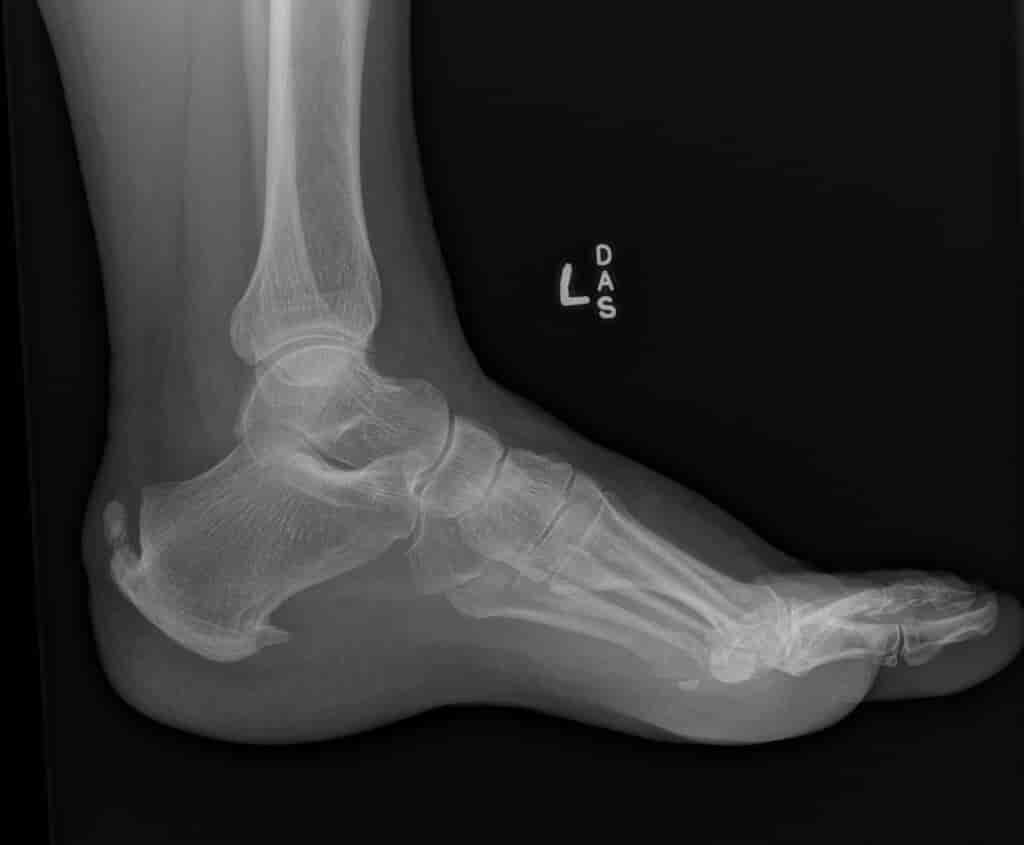

Haglund Deformity - Wikidoc

Haglund deformity - wikidoc www.wikidoc.org

haglund deformity radiology syndrome wikidoc retrocalcaneal calcaneal exostosis radiopaedia achilles bursitis bump associated heel bone imaging spurs saved choose board